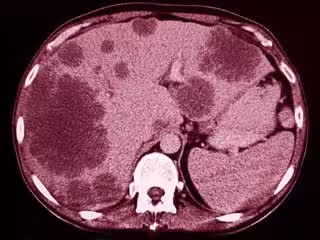

¿Cómo se despierta un cáncer dormido y hace metástasis?

Incluso después de un tratamiento exitoso contra el cáncer, las células cancerosas latentes que no se dividen y que previamente se desprendieron del tumor original pueden existir aún en cualquier parte del cuerpo. Si se despiertan, estas células pueden proliferar y convertirse en tumores metastásicos. Un equipo de CSHL que estudia la metástasis a los pulmones ahora ha identificado señales que acompañan a la inflamación que pueden despertar células cancerosas inactivas.